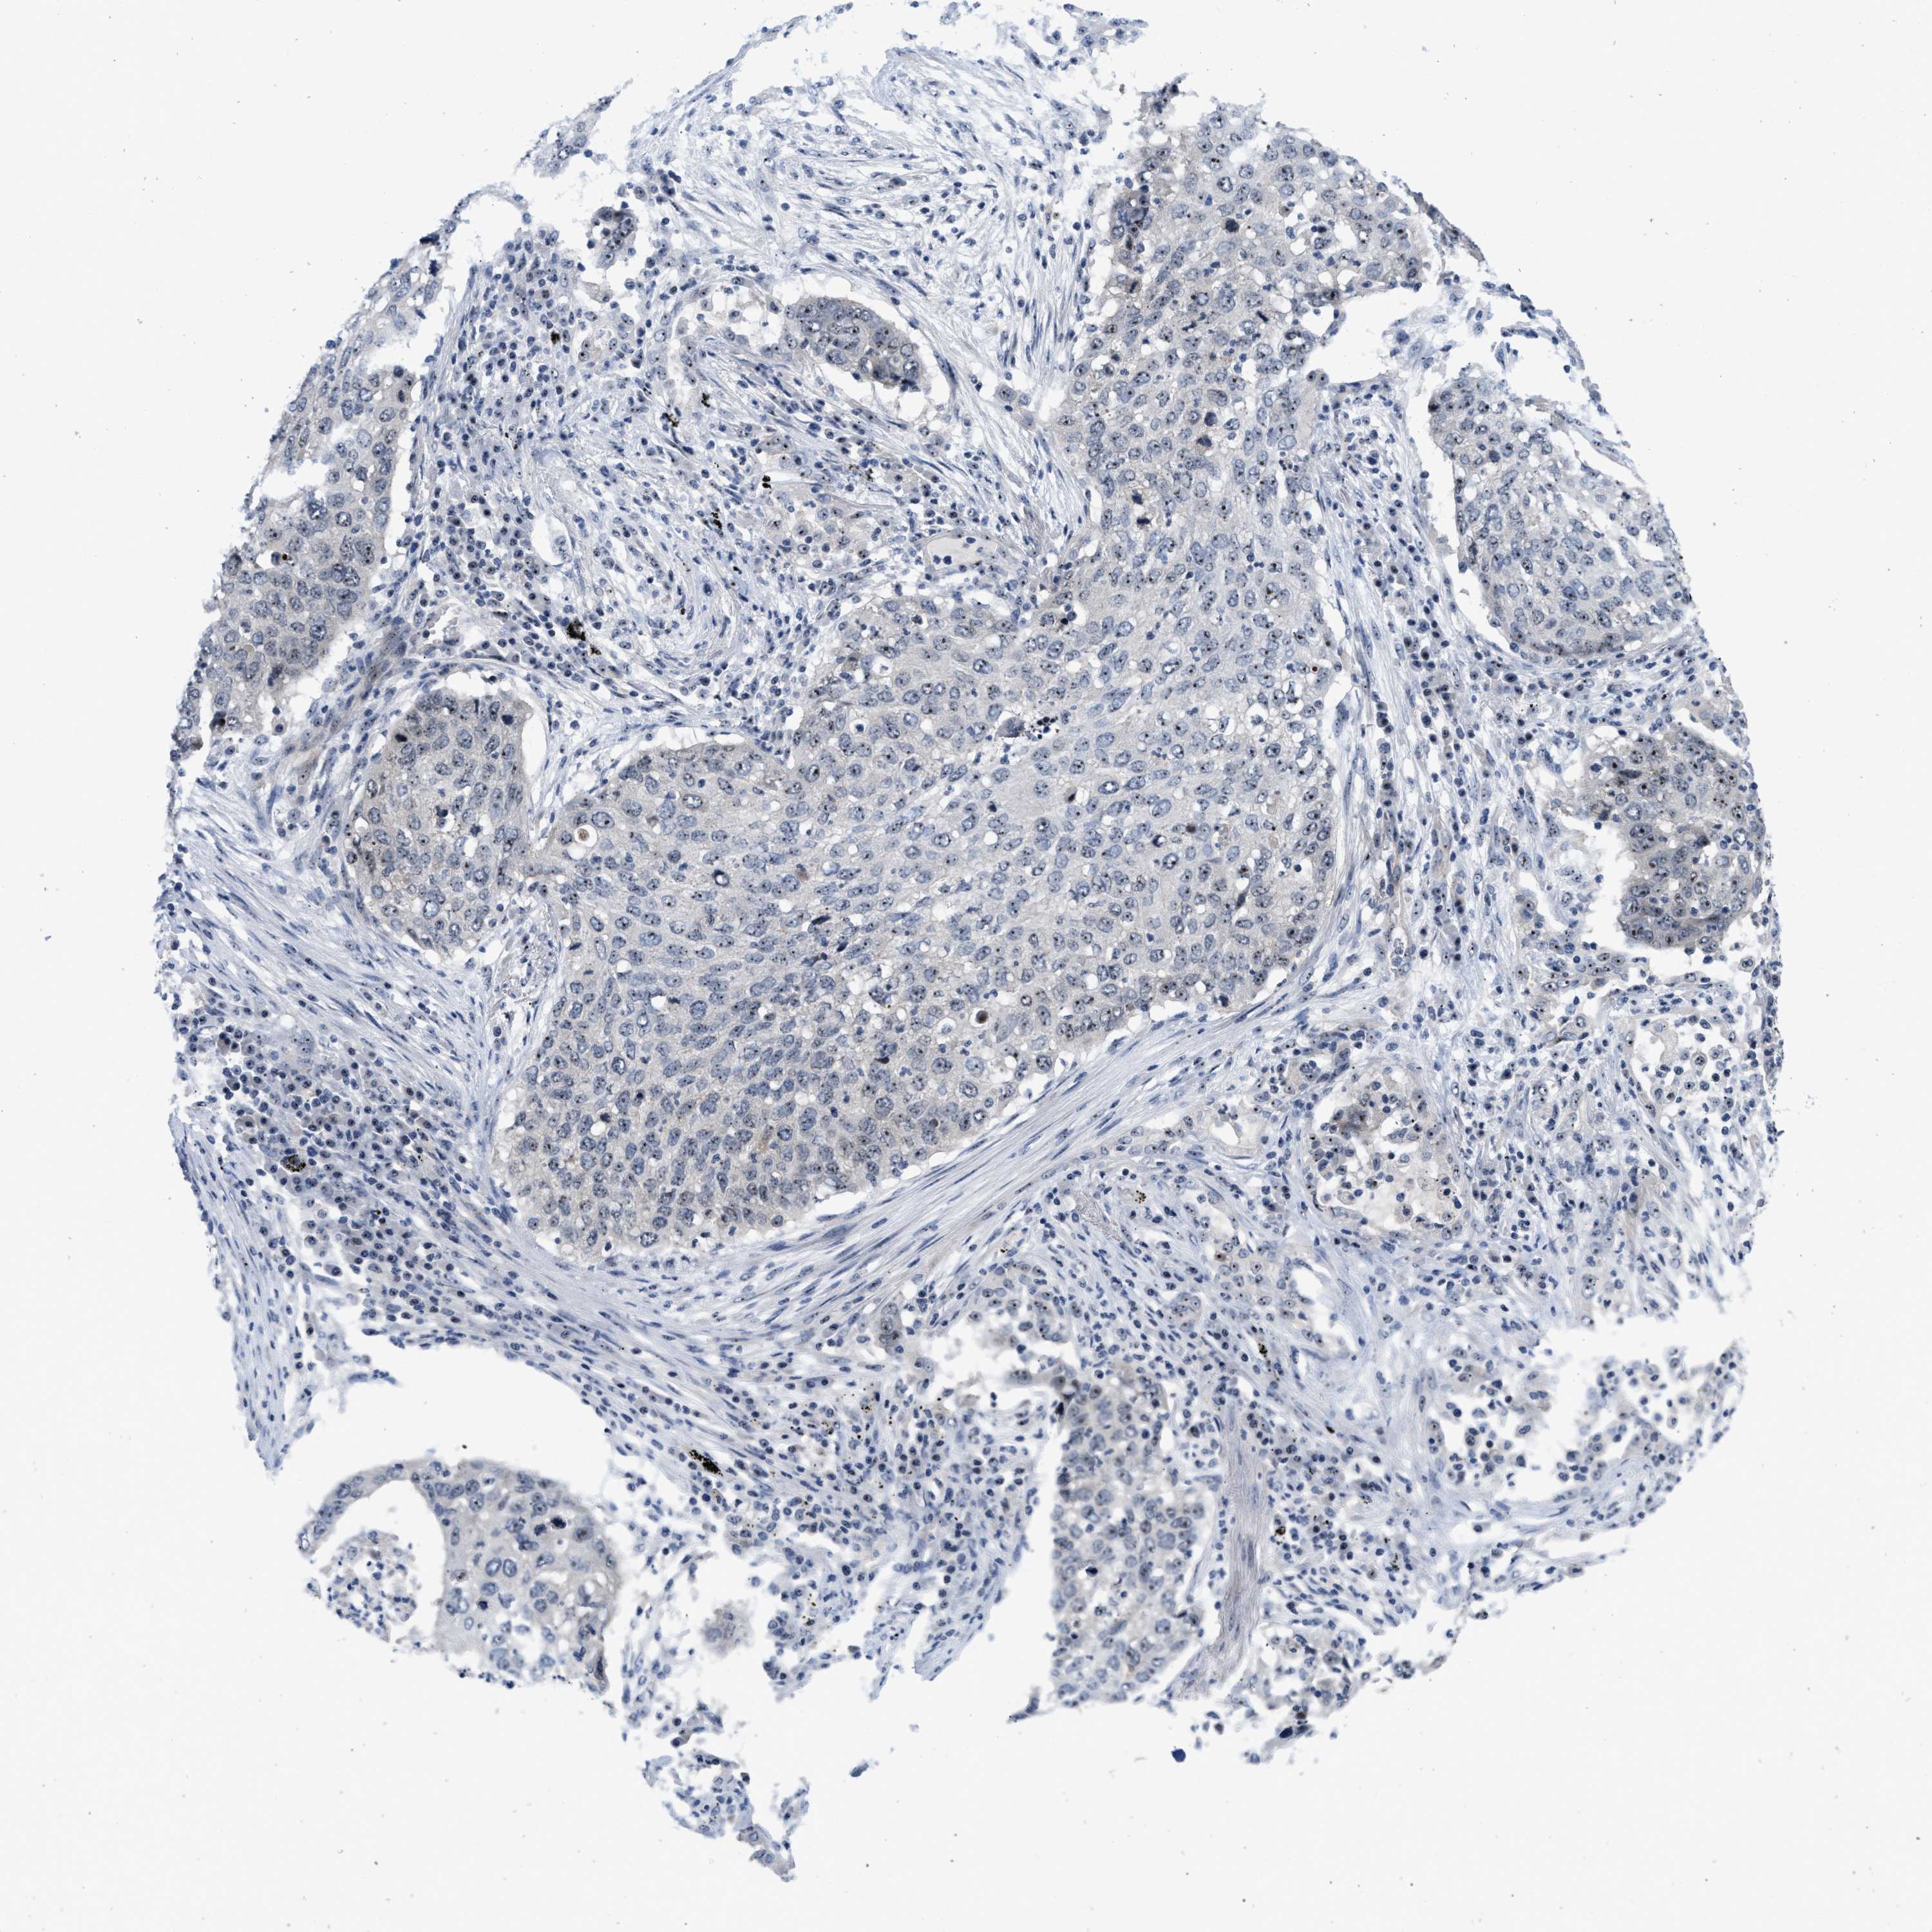

LUNG ADENOCARCINOMA (VALIDATION) - Interactive survival scatter ploti

The Survival Scatter plot shows the clinical status (i.e. dead or alive) for all individuals in the patient cohort, based on the same data that underlies the corresponding Kaplan-Meier plots. Patients that are alive at last time for follow-up are shown in blue and patients who have died during the study are shown in red.

The x-axis shows the expression levels (FPKM) of the investigated gene in the tumor tissue at the time of diagnosis. The y-axis shows the follow-up time after diagnosis (years). Both axes are complimented with kernel density curves demonstrating the data density over the axes. The top density plot shows the expression levels (FPKM) distribution among dead (red) and alive patients (blue). The right density plot shows the data density of the survived years of dead patients with high and low expression levels respectively, stratified using the cutoff indicated by the vertical dashed line through the Survival Scatter plot. This cutoff is automatically defined based on the FPKM cutoff that minimizes the p-score. The cutoff can be changed by dragging the vertical line or by entering a cutoff value in the square labeled "Current cut-off".

Under the Survival Scatter plot the p-score landscape (black curve; left axis) is shown together with dead median separation (red curve; right axis). Dead median separation is the difference in median mRNA expression between patients who have died with high and low expression, respectively. It is calculated as follows: median FPKM expression of dead patients with high expression - median FPKM expression of dead patients with low expression. This is intended to aid the user in visually exploring custom cutoffs and the associated p-scores and dead median separation.

Individual patient data is displayed and can be filtered by clicking on one or more of the category buttons on the top of the page. Categories describing expression level and patient information include: high, low, alive, dead, female, male and tumor stages. The scale of the x-axis can be toggled between linear and log-scale by clicking on the "x log" button. Mouse-over function shows TCGA ID, patient information and mRNA expression (FPKM) for each patient.

& Survival analysisi

Kaplan-Meier plots summarize results from analysis of correlation between mRNA expression level and patient survival. Patients were divided based on level of expression into one of the two groups "low" (under cut off) or "high" (over cut off). X-axis shows time for survival (years) and y-axis shows the probability of survival, where 1.0 corresponds to 100 percent.

NOP58 is not prognostic in Lung Adenocarcinoma (validation)

: 73.73